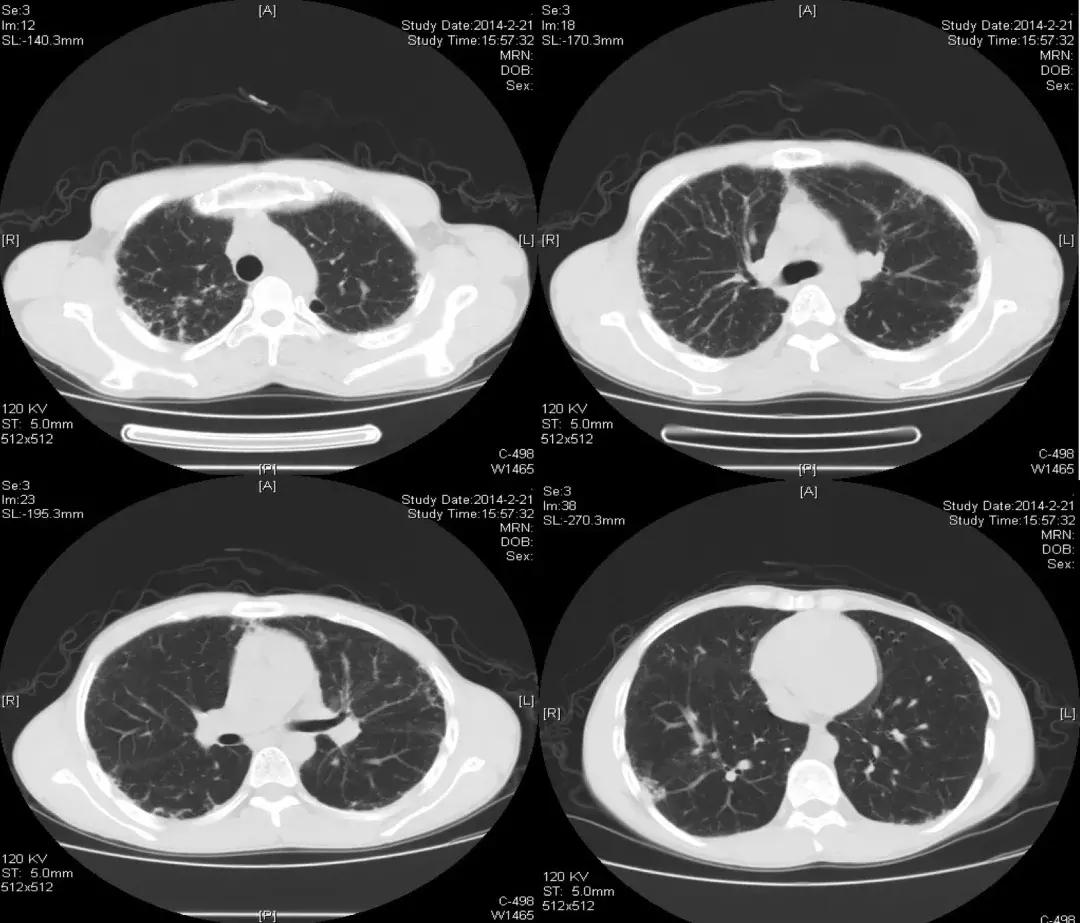

2014-02-21(入院第2天)胸部CT:

发现与2013-10-12胸部CT相似,主要还是以双上肺和胸膜下为主的网格状影,其次右下肺有片状影,可看到充气支气管征。

胸部CT(2017-07-11):

胸部CT(2018-02-22):